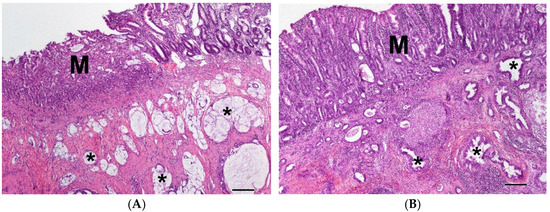

3.1.4. Carcinoma Cases (Groups 4S and 4L)